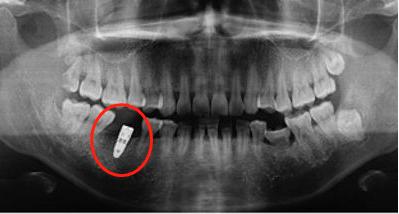

1,使用"非法种植体"。一般来讲,用于种植牙手术的种植体不论是进口还是国产的,都有严格的质量保障体系,材质的使用上也是领域内比较先进的,都是需要符合国家领域标准的。

有些低价的种植体是商家为了压低成本吸引消费者从一些地下工厂购买的"水货"。这些产品的质量得不到保证,有些患者在种植低价的种植牙后一两年便出现了种植体松动脱落的问题。

有患者因为贪图低价,种植了质量没有保障的种植体,短短一两年的时间就出现了种植体松动的现象,没到五年整个种植体就报废了。这比有质量保障的种植体十年以上存活率85%要低了很多。可见低价的种植体质量得不到保障,使用年限也就成了问题。